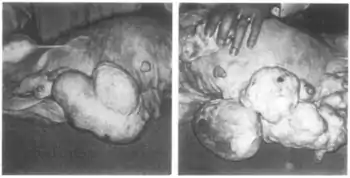

In combination with mestranol, similarly to ethynerone and anagestone acetate (and certain other progestogens, including progesterone and several other 17α-hydroxyprogesterone derivatives), chloroethynylnorgestrel was found to produce striking mammary tumors in beagle dogs after administration at very high dosages (10- to 25-fold human clinical dosages) for prolonged periods of time.[1][3][4] This resulted in the discontinuation of its development, along with that of ethynerone and anagestone acetate, as well as the removal of several progestins, including chlormadinone acetate, medroxyprogesterone acetate, and megestrol acetate, from various markets as contraceptives (although medroxyprogesterone acetate has since been reintroduced).[1][5] Subsequent research revealed that the risk is species-dependent and unique to canines and that there is no similar risk for humans.[6]